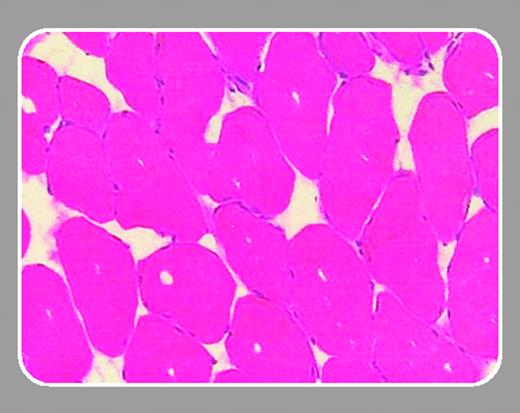

Arruda and colleagues (page 85) report an extension to their previous assessment of adeno-associated virus (AAV)–mediated factor IX delivery to skeletal muscle. In this study, the authors have evaluated the relative efficacy and safety of factor IX expression derived from 3 different AAV serotypes, the most frequently used AAV-2, and AAV-1 and AAV-6. Their investigations, in mice and dogs, show that the expression of factor IX is 10- to 50-fold higher following AAV-1 delivery compared with similar doses of an AAV-2 vector. This finding confirms earlier reports of enhanced transgene expression with intramuscular delivery by AAV-1, although the extent of this enhancement has varied considerably.4 Interestingly, the improvement in factor IX expression is only partially explained by the 2- to 3-fold increased transduction efficiency with the AAV-1 vector, and thus, other yet-to-be characterized mechanisms provide the biosynthetic advantage seen with this AAV serotype.